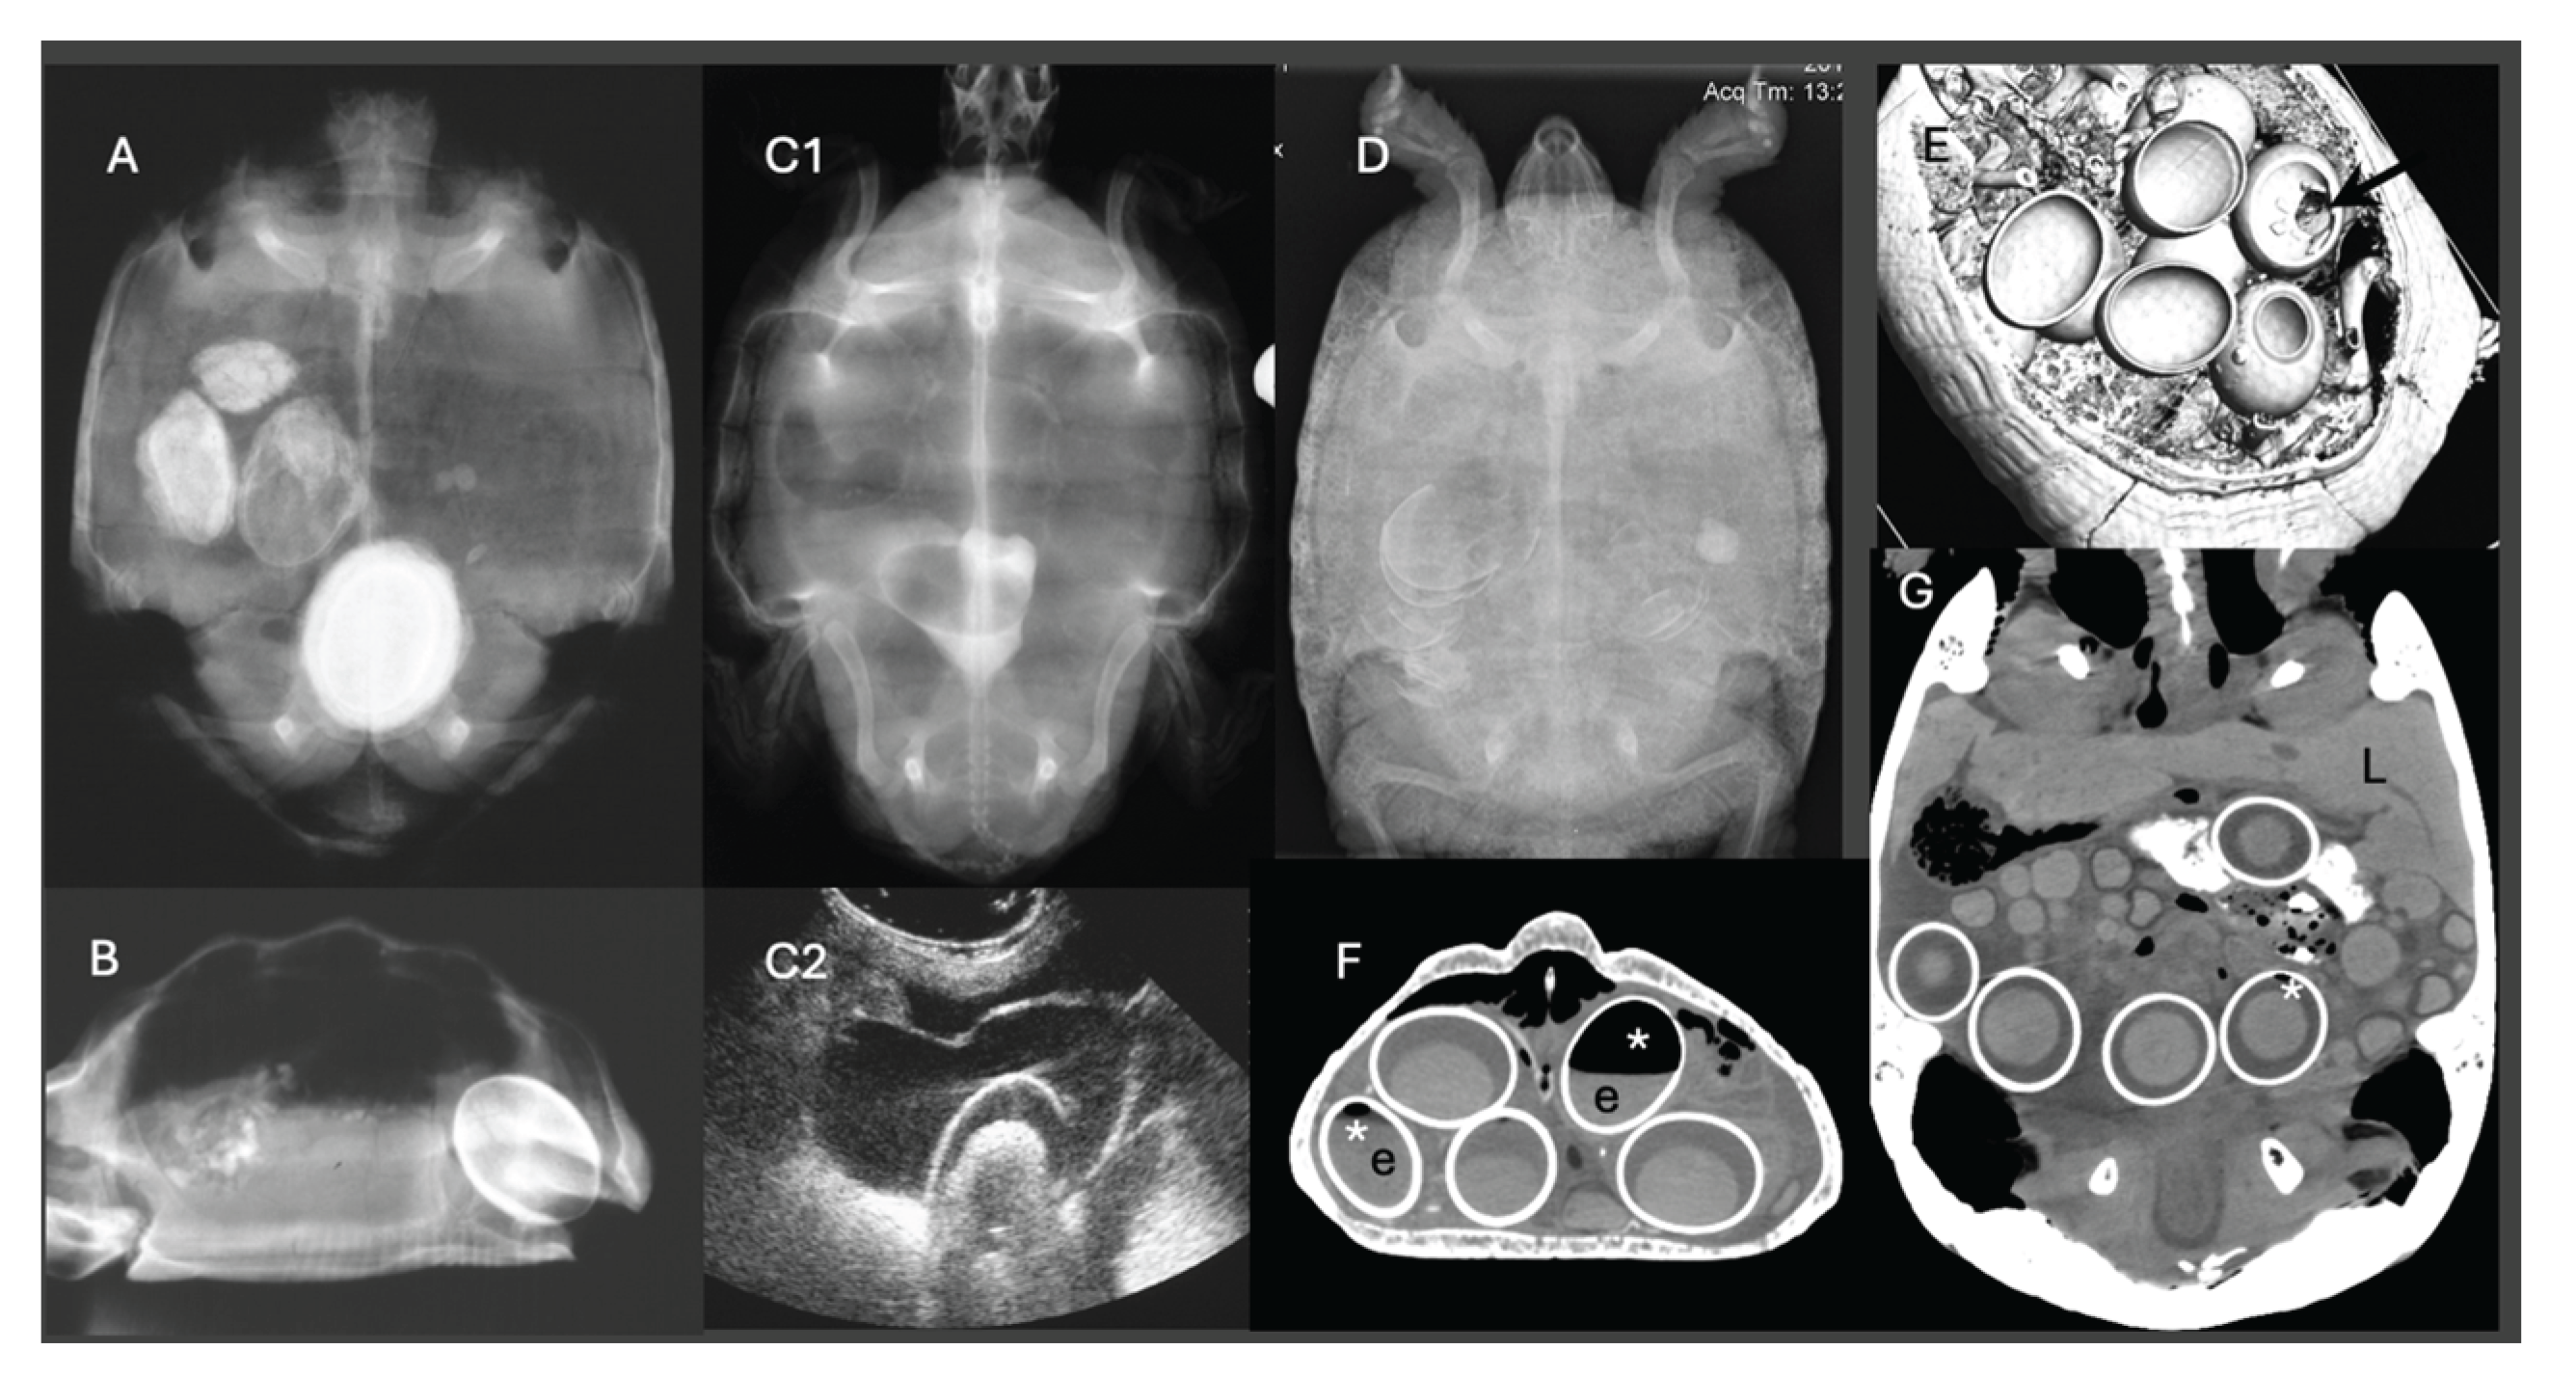

- Gumpenberger, M. Diagnostic imaging of reproductive tract disorders in reptiles. Vet. Clin. N. Am. Exot. Anim. Pract. 2017, 20(2), 327–343. [Google Scholar] [CrossRef]